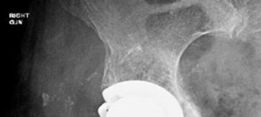

Revision THA Acetabulum Paprosky Type IIIA. ARMD with Metallosis with Severe Periacetabular Osteolysis and Co…